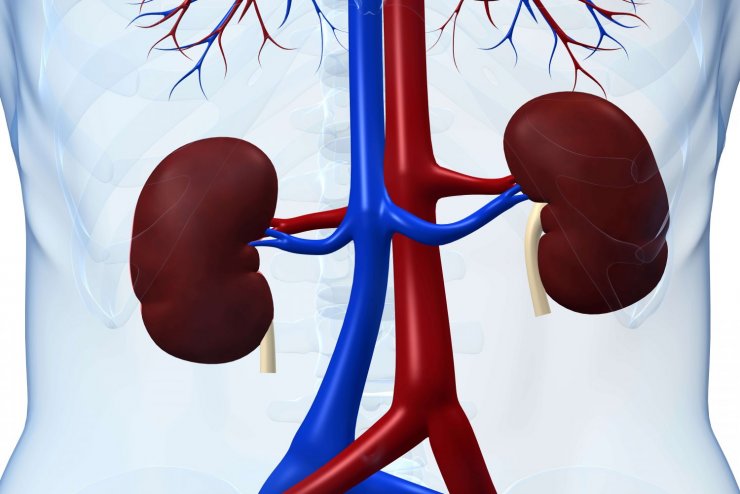

Eine Folge von Diabetes mellitus, insbesondere mit einem begleitenden Bluthochdruck kann eine diabetische Nephropathie sein, die zu einem dauerhaften Versagen der Nieren führen kann. Die Vor- oder Nachteile einer diagnostisch-therapeutischen Strategie mit einer Proteomanalyse des Urins im Vergleich zur konventionellen diagnostisch-therapeutischen Strategie, um durch eine frühzeitige Diagnose und Therapie Nierenerkrankungen zu vermeiden, hat das Institut für Qualität und Wirtschaftlichkeit im Gesundheitswesen (IQWiG) nun in einem Rapid Report untersucht.